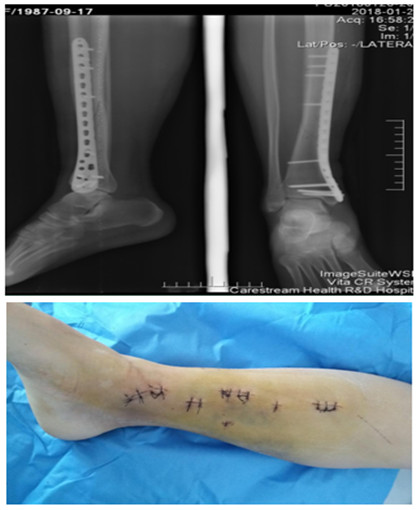

我院首例掌骨頸骨折髓內(nèi)釘技術(shù)